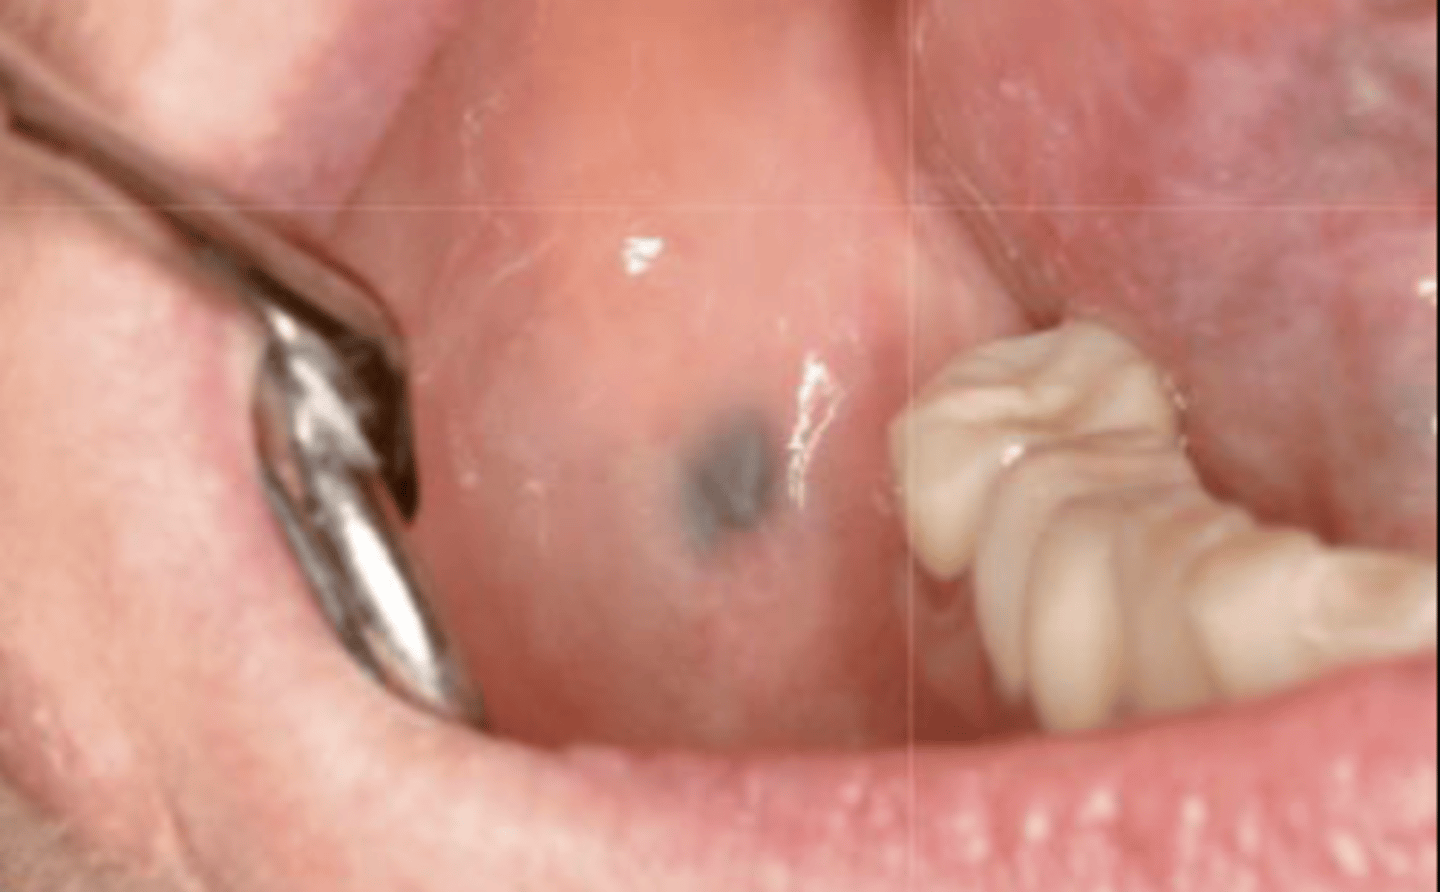

What type of pigmented lesion?

amalgam tattoo

These are clinical features of what?

- Asymptomatic, localized

- Blue-gray macule

- Localized around areas with amalgam restorations

amalgam tattoos

What is the most common location of amalgam tattoos?

gingiva/alveolar ridge mucosa (50%, then buccal mucosa, then floor of mouth)